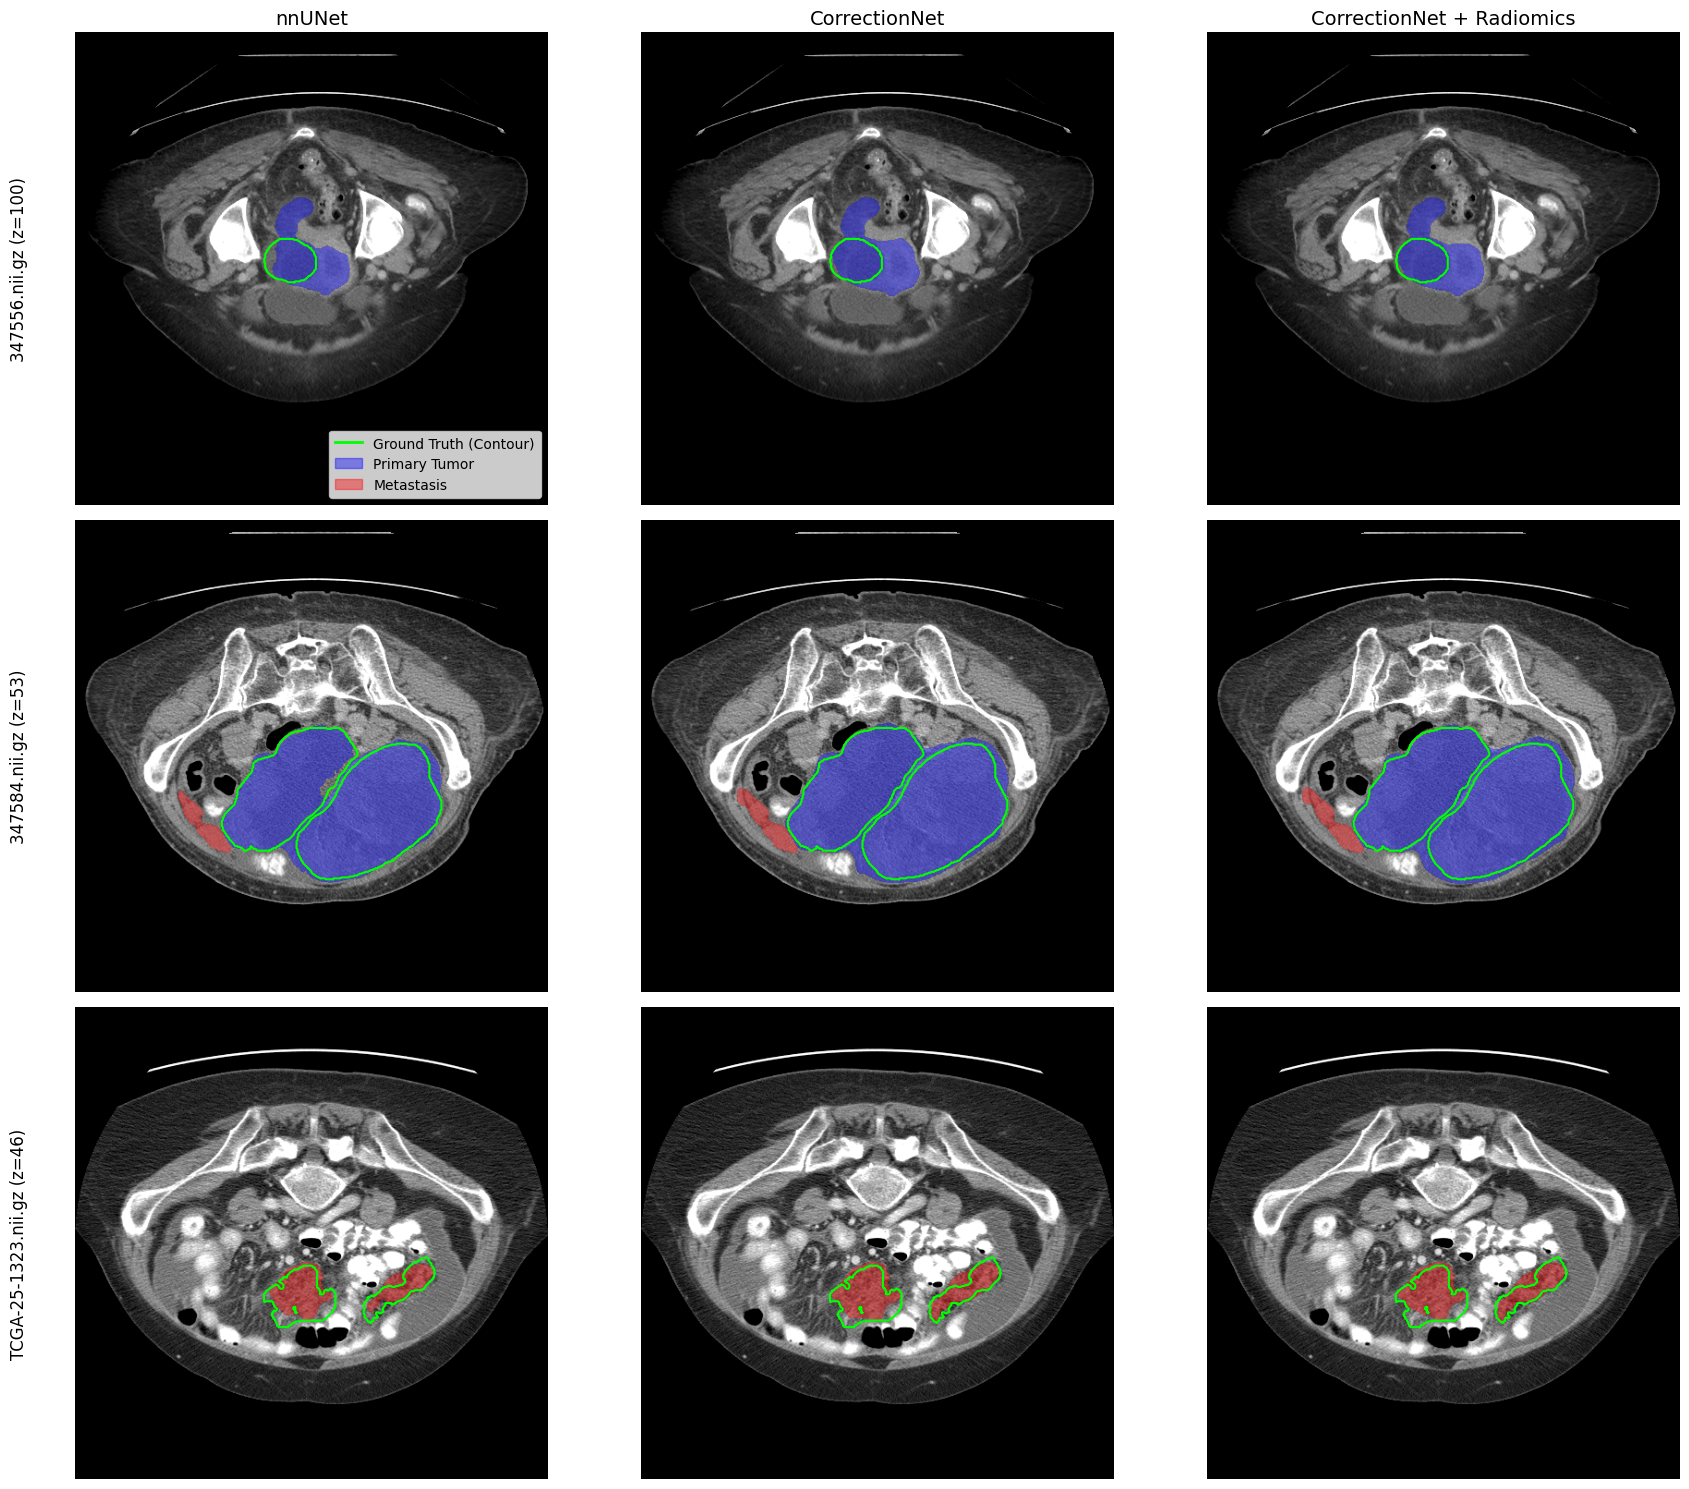

I recently completed my Master's in Computer Science with a focus on Data Science and AI from EPITECH (European Institute of Technology). I did my undergrad in Finance and Accounting at Paris School of Business where I graduated with high distinction. I am currently researching ways to improve deep learning–based segmentation for medical images using radiomics.

Publications & Research

Links will be available once the paper is published.